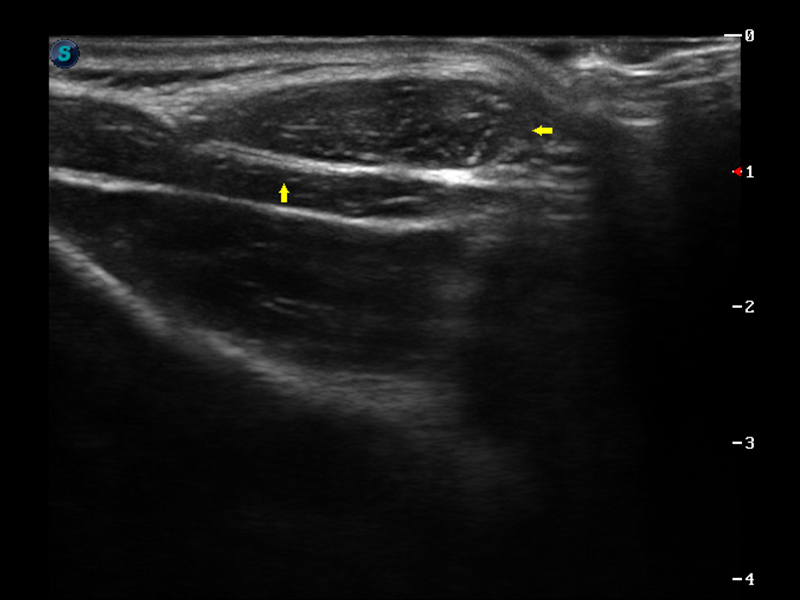

S9便携式彩色多普勒超声诊断仪是狗万官方网站研发的高端便携彩超设备,外观设计新颖、产品性能卓越。S9在便携超声领域采用了突破传统的触摸屏交互设计,并以先进的软件硬件技术和设计理念,为您带来清晰的图像质量、稳定的工作性能和便捷的操作体验。

VIS平台设计

μ-Scan微米成像

实时宽景成像